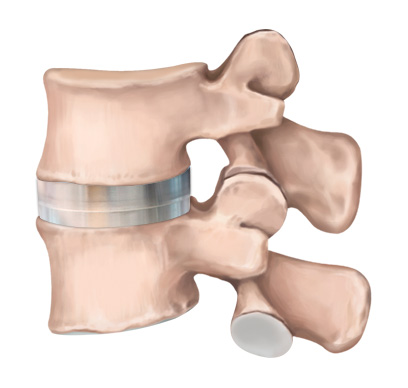

인공디스크 치환술은 손상된 디스크를 제거한 후 척추체 사이에 인공디스크를 삽입하여

본래의 디스크처럼 정상적인 기능을 하도록 하는 수술입니다.

STEP 01

손상된 디스크

STEP 02

손상된 디스크 제거

STEP 03

인공디스크 삽입